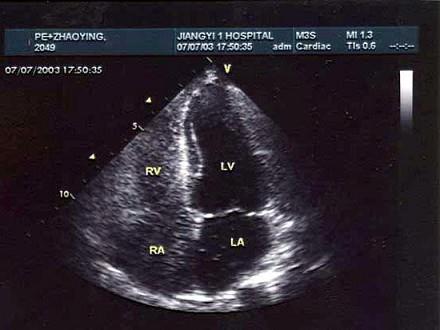

某患者行右心造影,心尖四腔心切面声像图所示,提示为?(?)A.室间隔缺损B.动脉导管未闭C.房间隔缺损D.正常结构E.二尖瓣狭窄

问题 某患者行右心造影,心尖四腔心切面声像图所示,提示为?(?)

选项 A.室间隔缺损 B.动脉导管未闭 C.房间隔缺损 D.正常结构 E.二尖瓣狭窄

答案 C